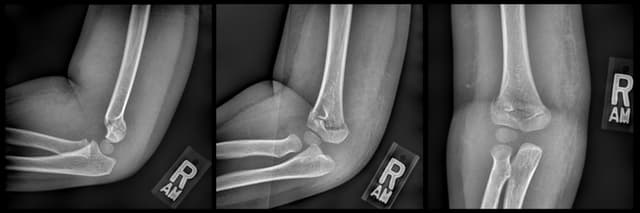

Supracondylar humerus CRPP

Pre-op

Post-op